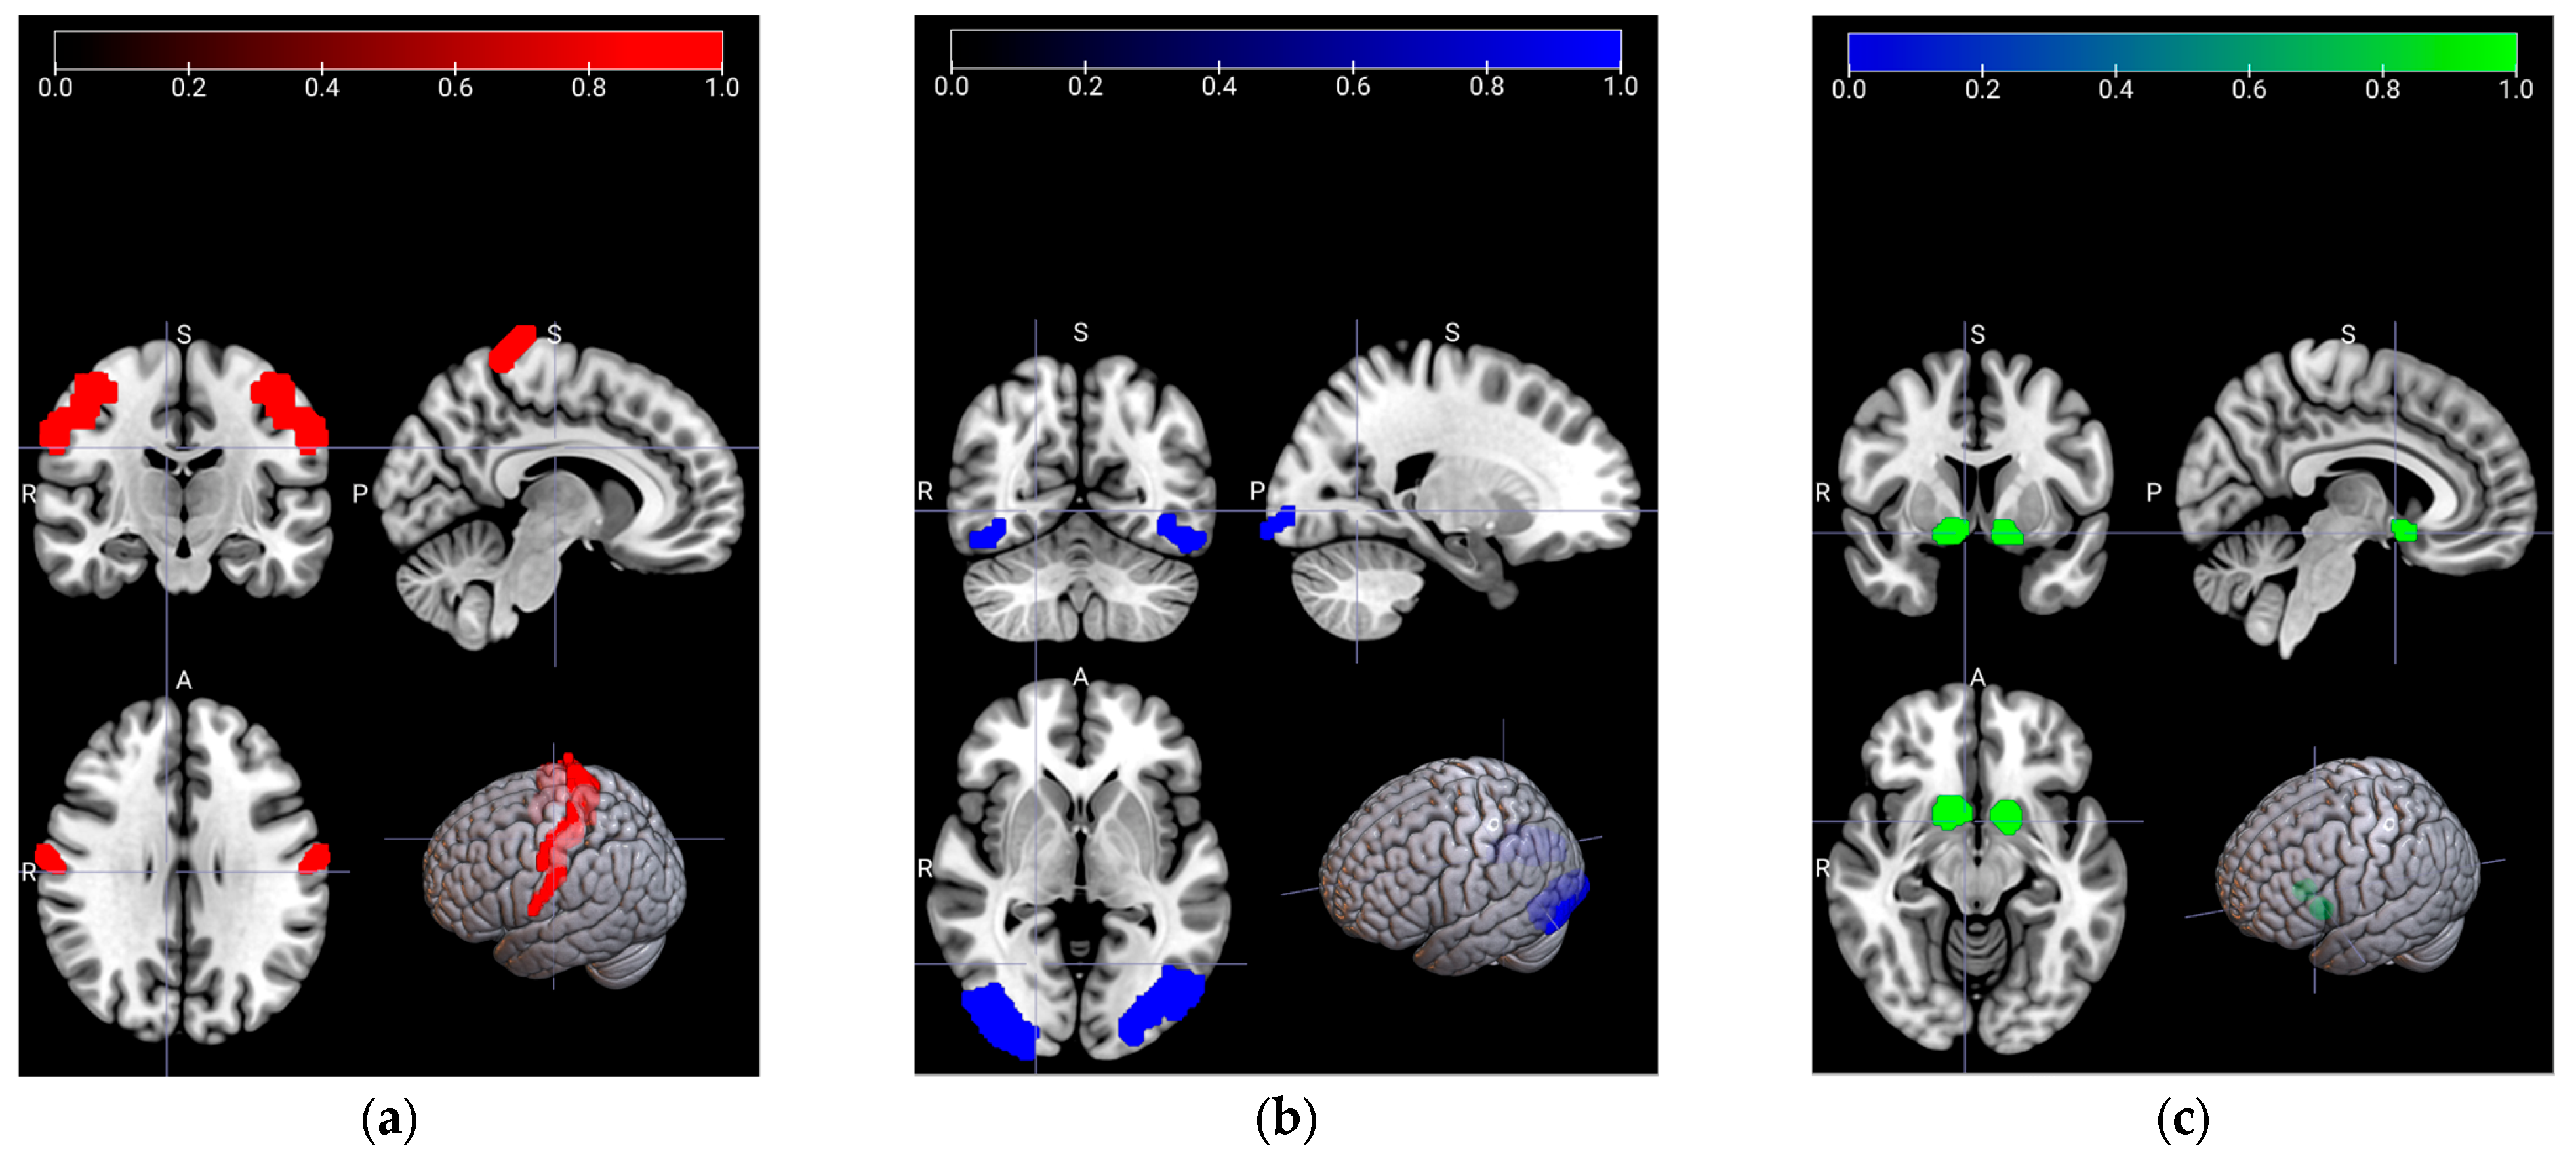

Region-of-Interest (ROI) selection is a sophisticated process, so it should be evaluated very carefully by the experts according to the hypothesis of the research question. The first step in determining the ROIs is to complete the first-level (individual level) for each subject and each task. The hypotheses are searched by the contrast vectors, which are based on the statistical inferences and on the functional data. Since the fMRI tasks are built on different hypotheses, the contrast vectors also differ for each task. This results in distinct ROIs among the fMRI tasks. The main point for the ROI selection is to be able to conduct the second-level (group level) analysis after completing the first-level analysis. Thus, the activation maps exhibit the active areas for the entire group. The signals have been revealed by experts from the determined ROIs, which are illustrated in Figure 2. Nucleus Accumbens (NAcc), associated with reward-related behaviors, is given in Figure 2a. In Figure 2b, Broadmann Area 4 (BA4) is shown, which is related to the motor movements for Em-fMRI. Finally, Occipital Face Area (OFA), which plays an important role for face processing and recognition, distinguishing familiar faces, and responding to face stimuli, is presented for the mem-fMRI in Figure 2c. For the rs-fMRI, the signals have been gathered from all the determined ROIs additionally.

Figure 2.

The region-of-interest (ROIs) of the task-related areas are illustrated in coronal, sagittal (top row), and axial (bottom row-left) anatomical sections, respectively, as well as with the locations in the rendered brain (bottom row-right). (a) Nucleus Accumbens (NAcc), shown in green, is associated with the reward-related activities; (b) Broadmann Area-4 (BA4), shown in red, is related to motor movements; (c) Occipital Face Area (OFA), shown in blue, is related to face processing and recognition.